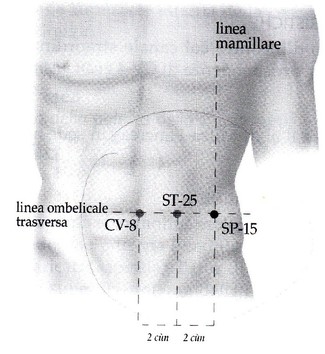

SP-15 daheng, grande tratto orizzontale

Si trova sulla linea dell'ombelico a 4 cun, da qui il nome "grande tratto orizzontale": la zona è molto importante per i problemi addominali dovuti alle funzioni del sistema Milza, e comprende anche i punti CV-8 shenque (sull'ombelico), KI-16 huangshu (del Chong Mai) e ST-25 tianshu. Viene utilizzato anche per rafforzare il Grosso Intestino nei casi per esempio di stipsi o di dolori. In altri casi dissolve l'Umidità negli Intestini che provocano diarrea. Siccome la zona tonifica la Milza viene usata anche per rafforzare le gambe in caso di debolezza o freddo. Infine favorendo il movimento del Qi è utile anche per i dolori addominali sul lato sinistro dovuti a stasi di Fegato.